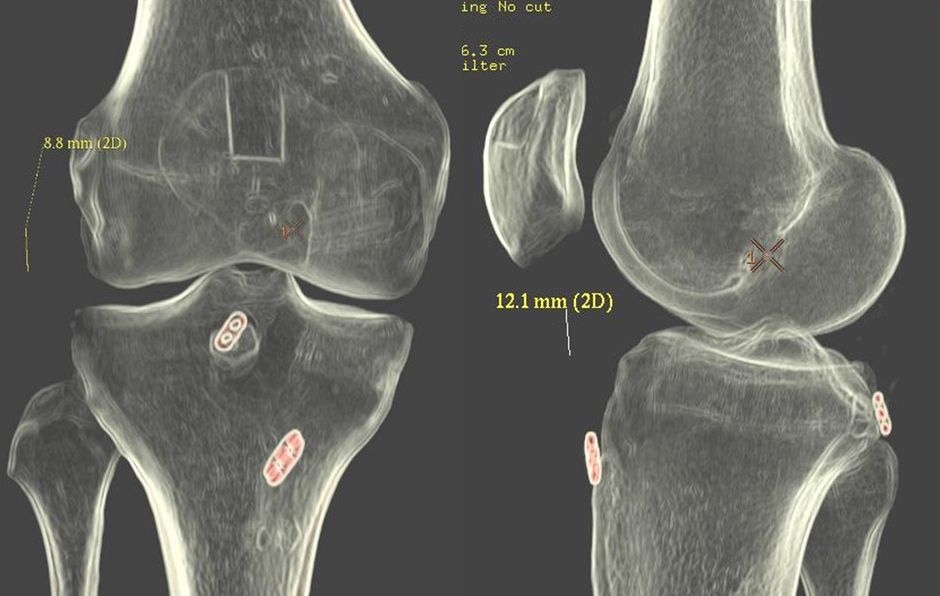

Postoperative X-rays control and CT imaging control is carried out for quality documentation. (Fig 27 + 28).

Fig 27 - Postoperative  x-rays

Fig 28 - Postoperative 3D CT for documentation of tunnel placement